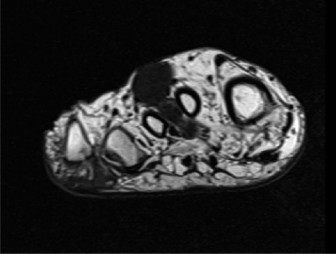

- Magnetic Resonance Imaging (MRI): The gold standard for local staging. It provides detailed information on tumor size, exact anatomical location, relationship to neurovascular bundles, bone, joints, and adjacent soft tissue compartments. T1-weighted, T2-weighted with fat suppression, and post-contrast T1-weighted sequences are typically utilized. MRI helps delineate the extent of peritumoral edema and identify skip lesions.

Figure 1: Pre-operative MRI depicting a soft tissue mass in the foot/ankle, illustrating its anatomical relationship to surrounding structures. High-resolution imaging is crucial for accurate staging and surgical planning in clear cell sarcoma. -